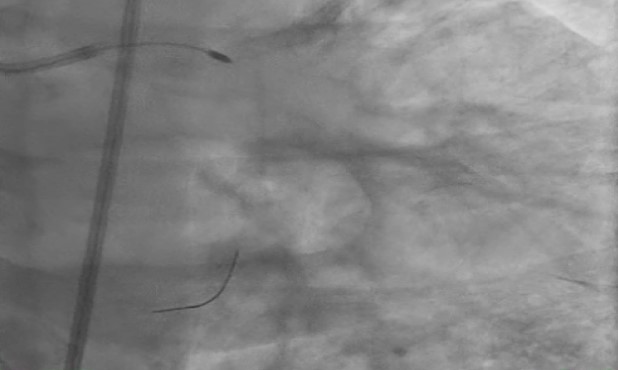

1) Proximal Left Anterior Descending artery's pre analysis done with OCT.2) Calcium arc on OCT displayed as 360 degrees with 800 micron thickness and length greater then 5mm with minimum Lumen Area of 1.83mm3) Intravascular Lithotripsy performed with focus on proximal Left Anterior Descending Artery4) Post Intravascular Lithotripsy procedure, Optical Coherence Tomography was performed5) The lumen gain obtained post procedure was equivalent to 5.24mm6) Stenting done7) LCX ostium with tight lesion with heavy calcification pre dilated with NC balloon and two stents placed.